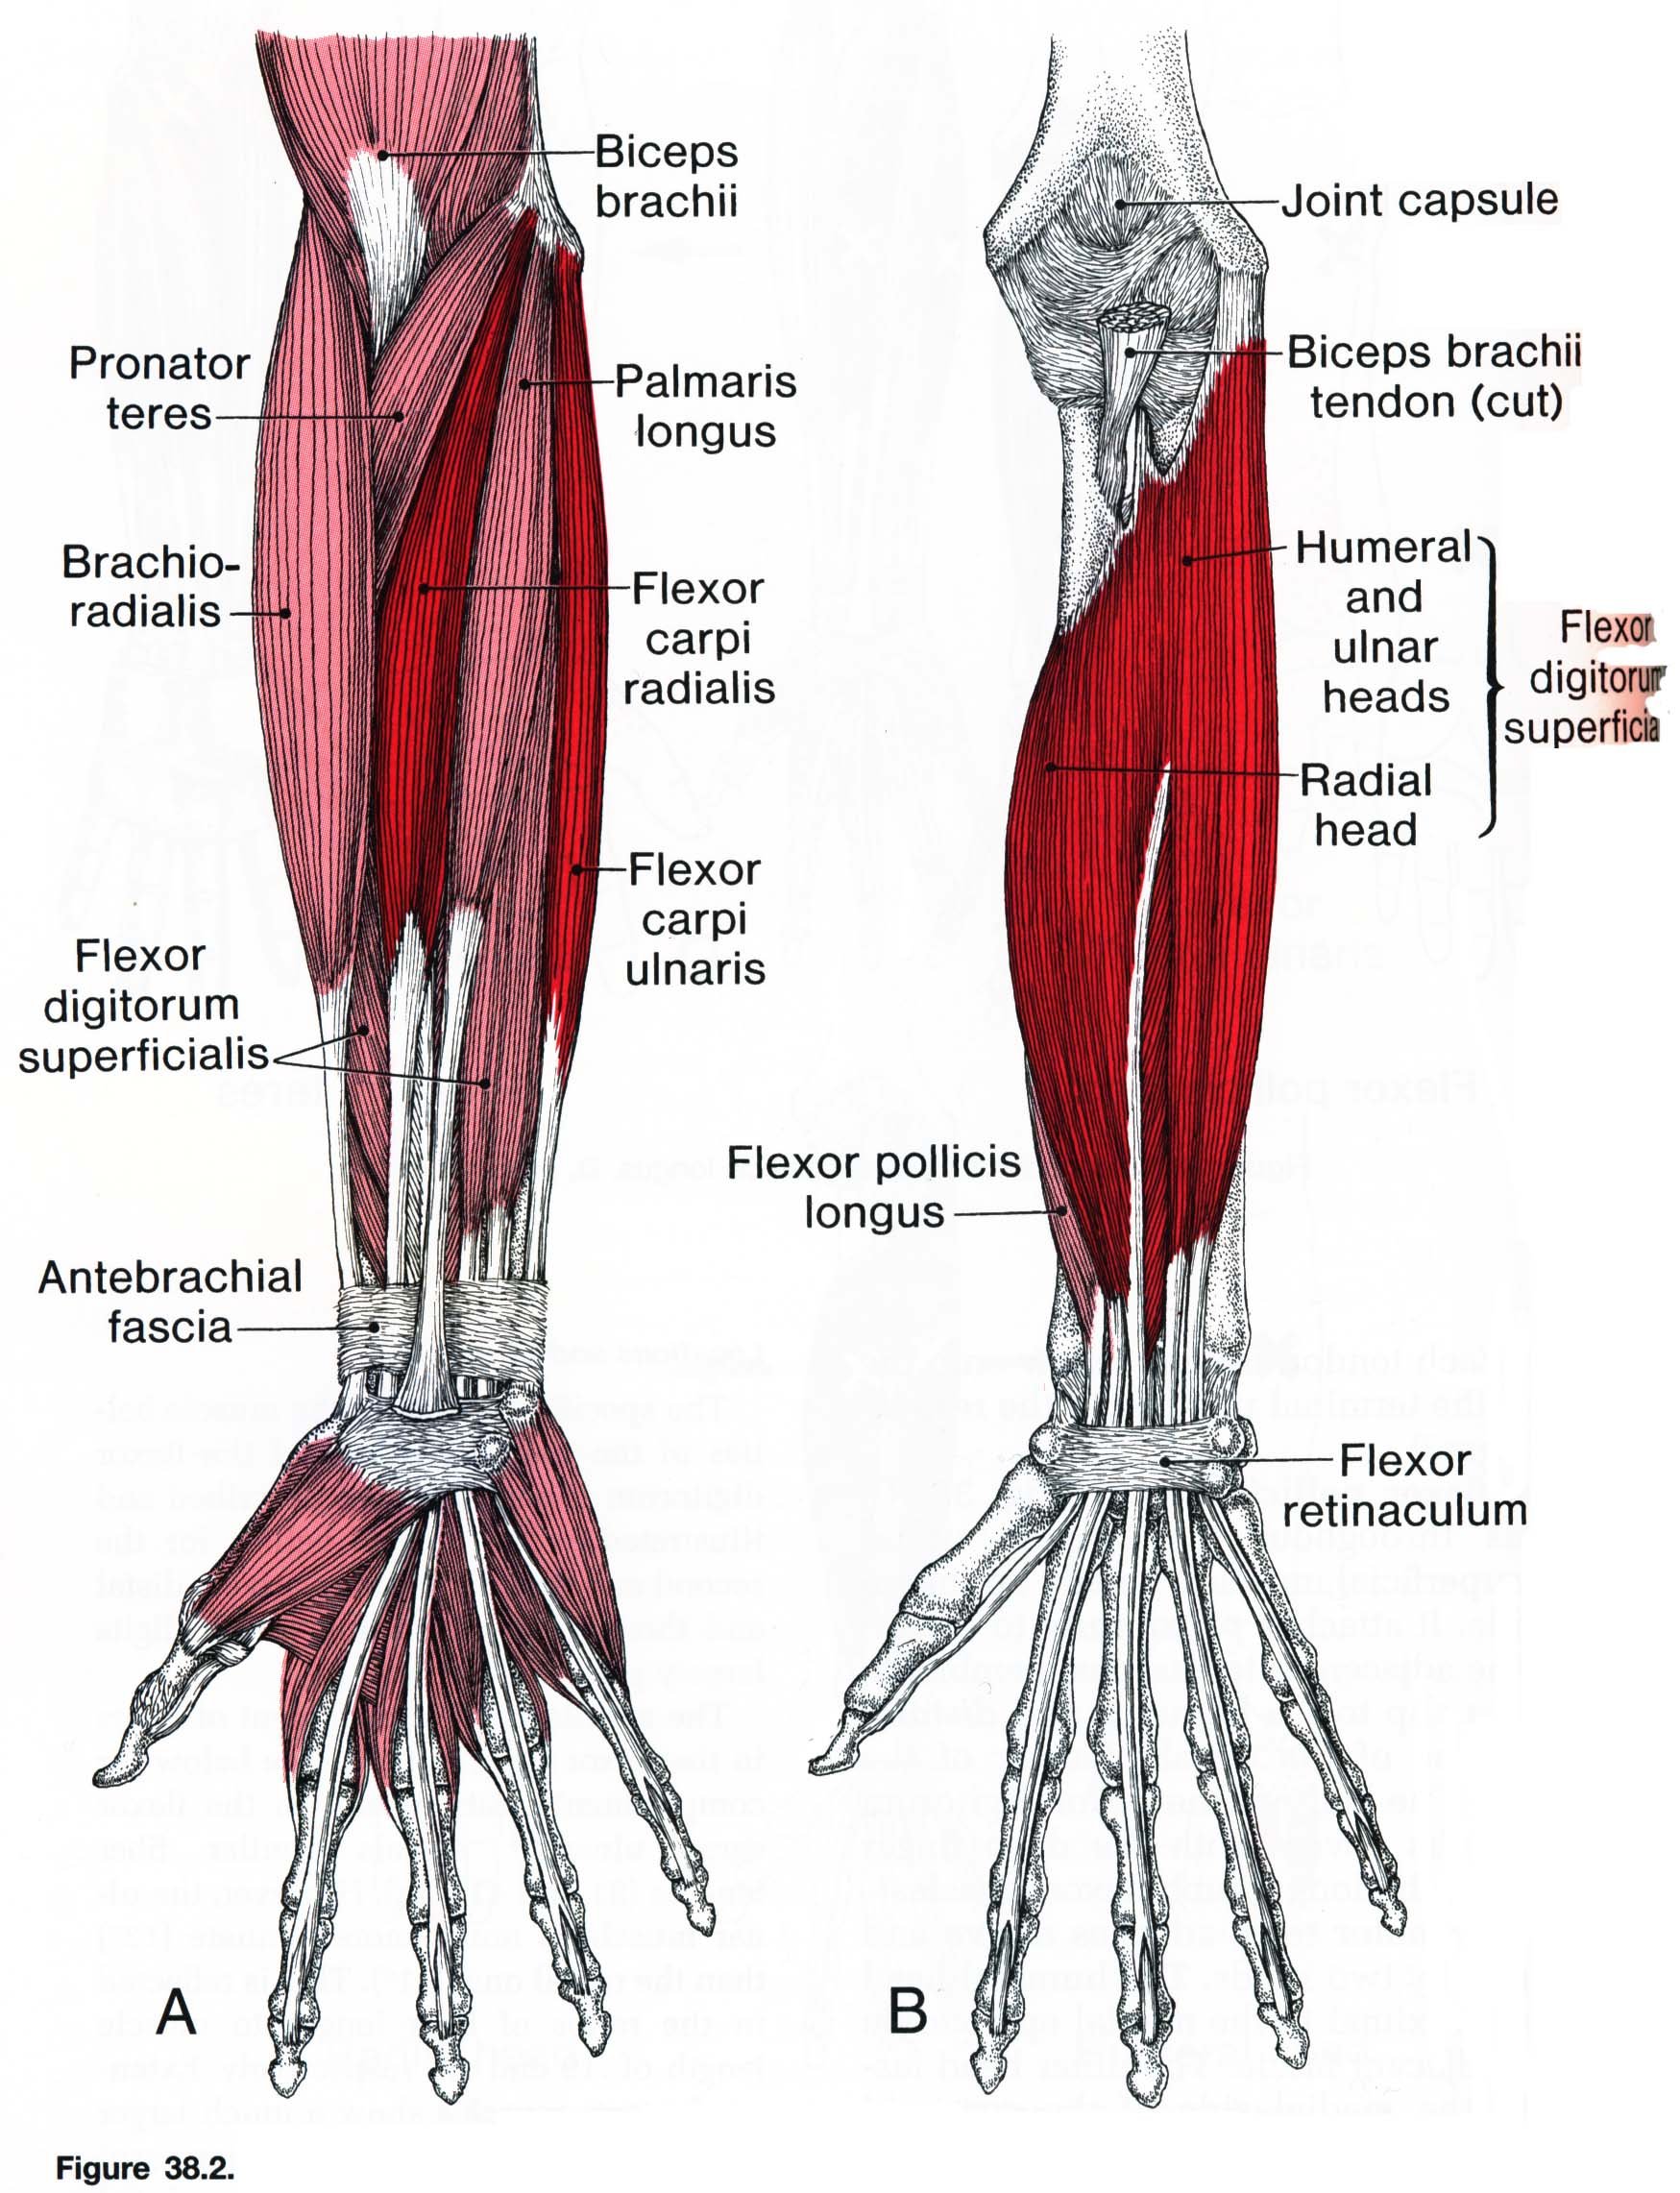

Анатомия мышцы Palmaris Longus